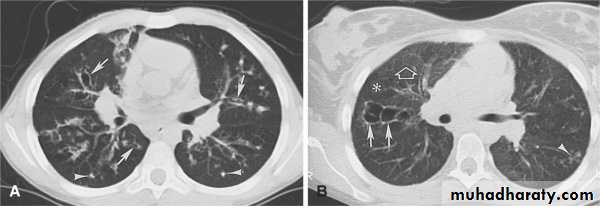

Bronchiectasis

Mucous in the airways cannot be easily cleared fromthe lungs